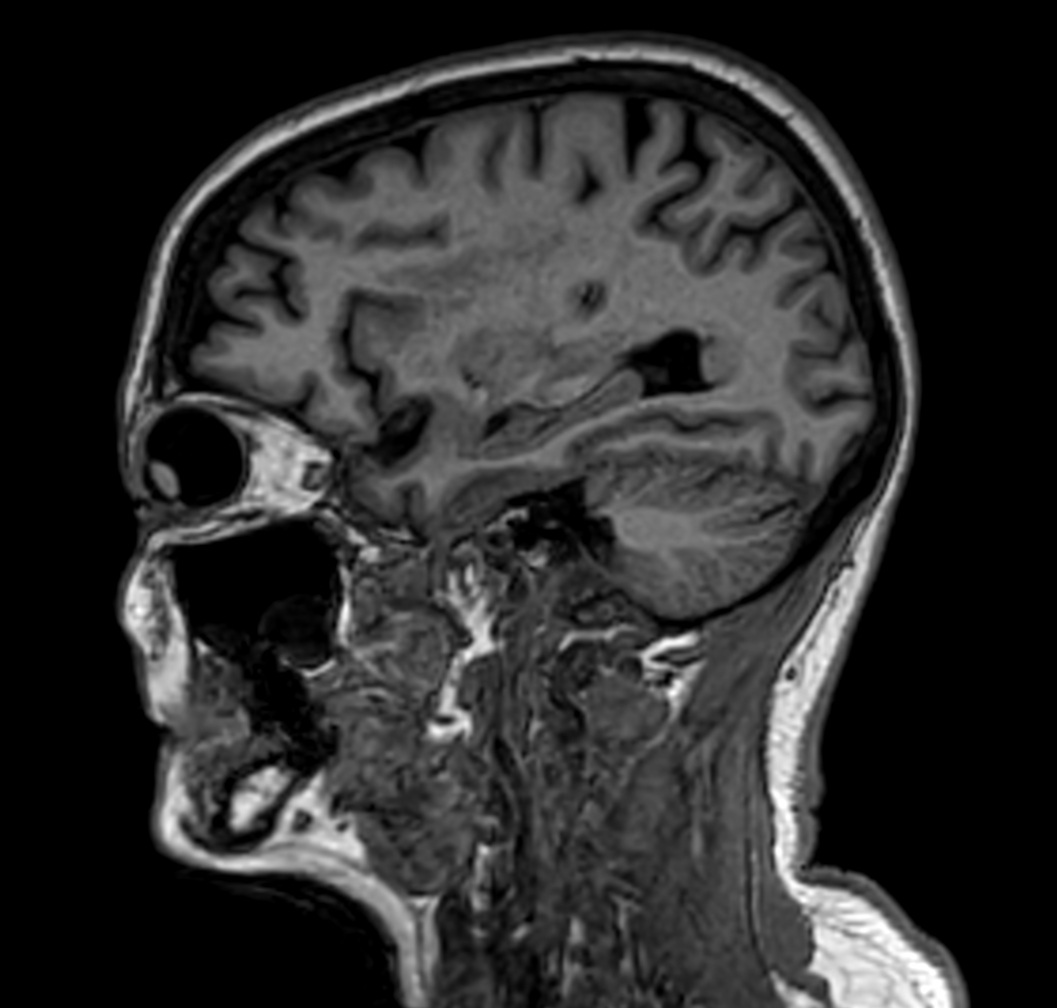

Sagittal 3D VIEW - T1w TFE